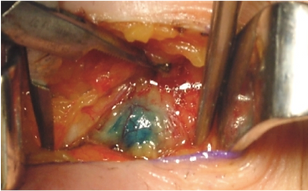

Pesquisa do linfonodo sentinela: é um procedimento de grande importância no estadiamento do melanoma cutâneo. Consiste em um método-padrão para saber se o câncer atingiu linfonodos em pacientes com melanoma e quando os linfonodos não parecem clinicamente aumentados. Uma substância radioativa é injetada no melanoma ou na cicatriz da biópsia prévia e uma hora depois os linfonodos são examinados para ver qual deles é o primeiro a drenar a região do melanoma. Durante a cirurgia, novamente uma substância é injetada na lesão, um contraste azul, para que também vá para o primeiro nódulo a receber a drenagem linfática do tumor, que é o chamado linfonodo sentinela. O linfonodo é identificado através da utilização de um aparelho chamado gamaprobe que ajuda na sua localização. A biopsia é realizada e encaminhada para estudo anátomo-patológico com cortes seriados, na tentativa de se identificar a presença de micrometástases. Se este linfonodo mostrar acometimento pelo melanoma, todos os demais daquela região devem ser removidos. Se não houver células cancerosa, não há necessidade de remover os demais.

Figura 1: desenho ilustrativo de injeção de azul patente no melanoma e migralçao pelo sistema linfático até o linfonodo sentinela. Figura 2: pesquisa intra-operatória de linfonodo sentinela com gammaprobe. Figura 3: identificação de linfonodo sentinela corado pelo azul patente.